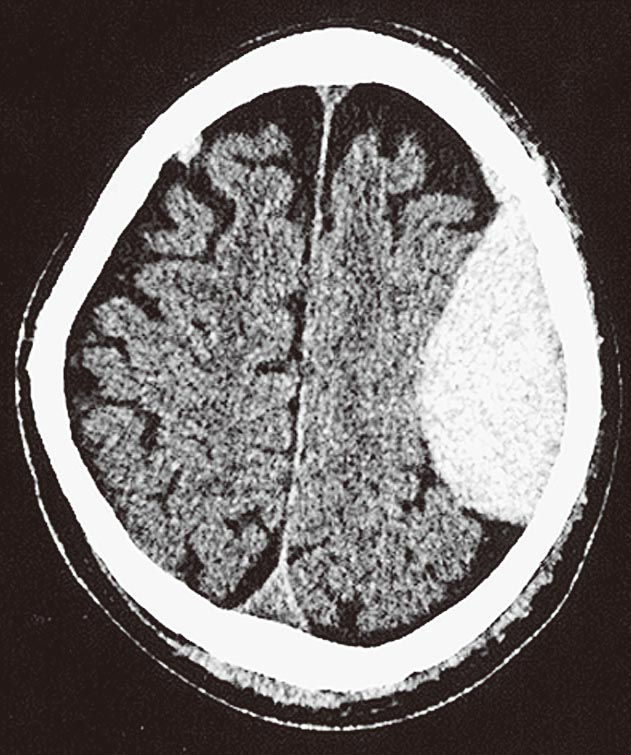

頭部CTを下に示す.所見として

- 1.硬膜外血腫

- 2.硬膜下血腫

- 3.皮質下出血

- 4.くも膜下出血

- 5.脳動静脈奇形

解答: 1